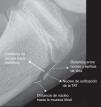

ConclusiónLa osificación de la TTA se inicia distalmente, posteriormente se fusiona su parte proximal con el resto de la epífisis y finalmente se fusiona en su parte distal a la tibia. Este estudio ayuda a un mejor análisis de la TTA cuando nos enfrentamos a un dolor de rodilla.

ConclusionThe ossification of the anterior tibial tuberosity starts distally, then the proximal part fuses with the rest of the epiphysis, and finally the distal part fuses with the tibia. The results of this study help enable a better analysis of the anterior tibial tuberosity in cases of knee pain.